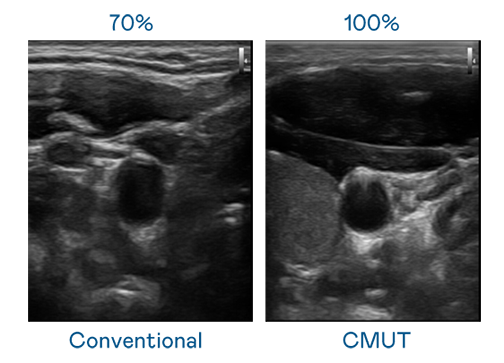

CMUT 技術是一種用電容式微機電元件來產生超音波訊號的技術。與傳統 PZT 壓電式技術相比,CMUT 頻寬增加 30%,更寬頻的超音波訊號讓影像解析度大幅提升,是實現高影像品質醫療超音波掃描、促進精準醫療發展的關鍵技術。

大頻寬帶來超清晰影像

超音波影像的解析度高低,首先取決於探頭能發出的訊號頻寬。ag亚娱 CMUT 可提供高清晰的超音波訊號,提供高頻寬、高靈敏度、影像紋理細節更高的超音波影像,協助醫護人員縮短影像判讀時間及利用精準的醫療影像進行診斷。